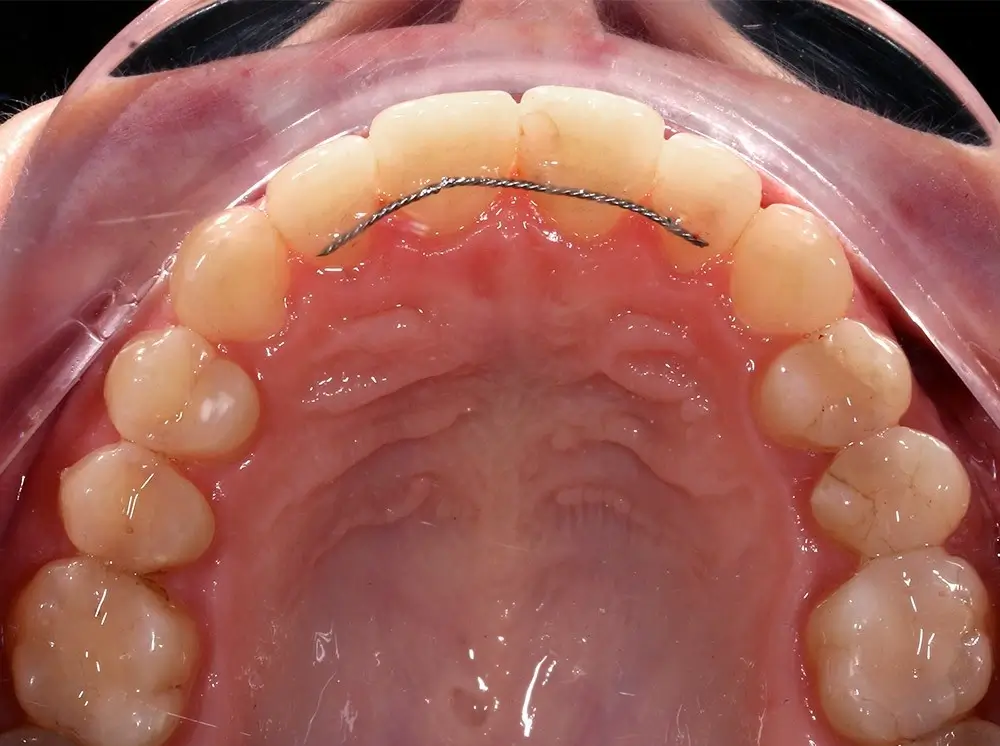

Кейс 13

Булгач (Мочалова) Галина Игоревна

Количество кап ВЧ 19

Количество кап НЧ 24

ДО

ПОСЛЕ